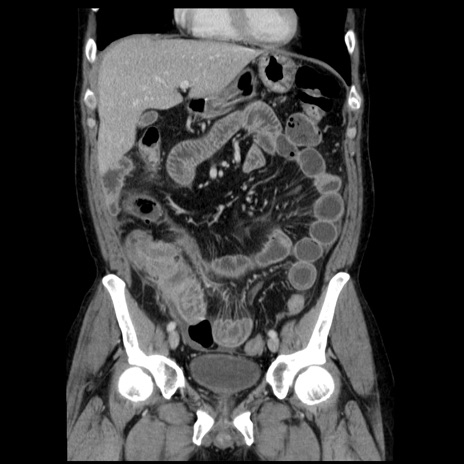

症例29(冠状断像)

【症例】40歳代男性

【現病歴】2日前から胃痛あり。徐々に周期的な激痛に変化した。本日になっても激痛があるため受診。

【身体所見】意識清明、BT 38-39℃台あり、腹部:膨満、やや硬、右下腹部に圧痛あり。

【データ】WBC 8500、CRP 23.26